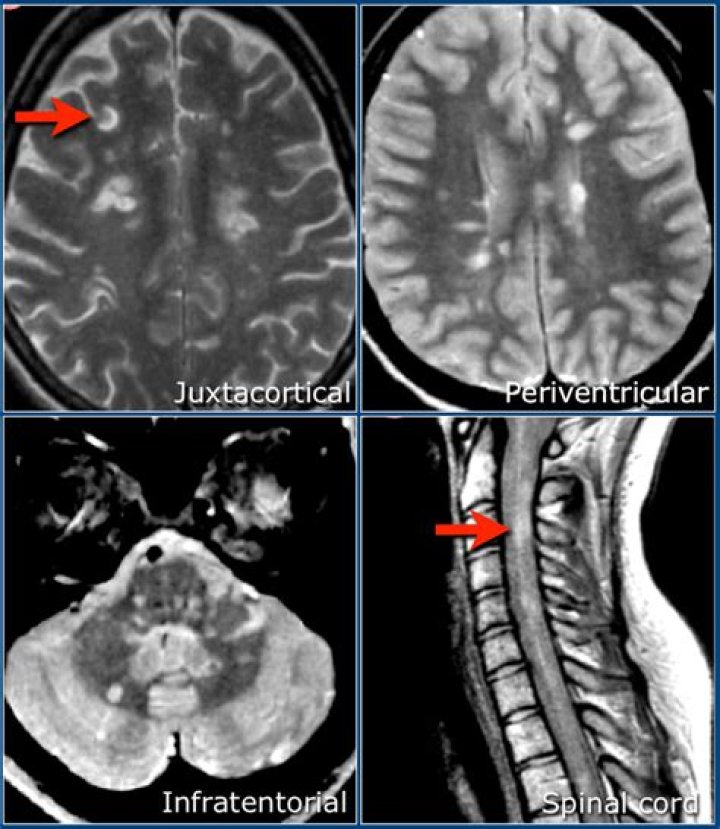

Under the McDonald Criteria (revised), an MS diagnosis is likely if myelin damage is disseminated in space, as seen in an MRI as: At least one T2 bright lesion in at least two or four CNS locations: the juxtacortical, perventricular and infratentorial areas of the brain, and the spinal cord.